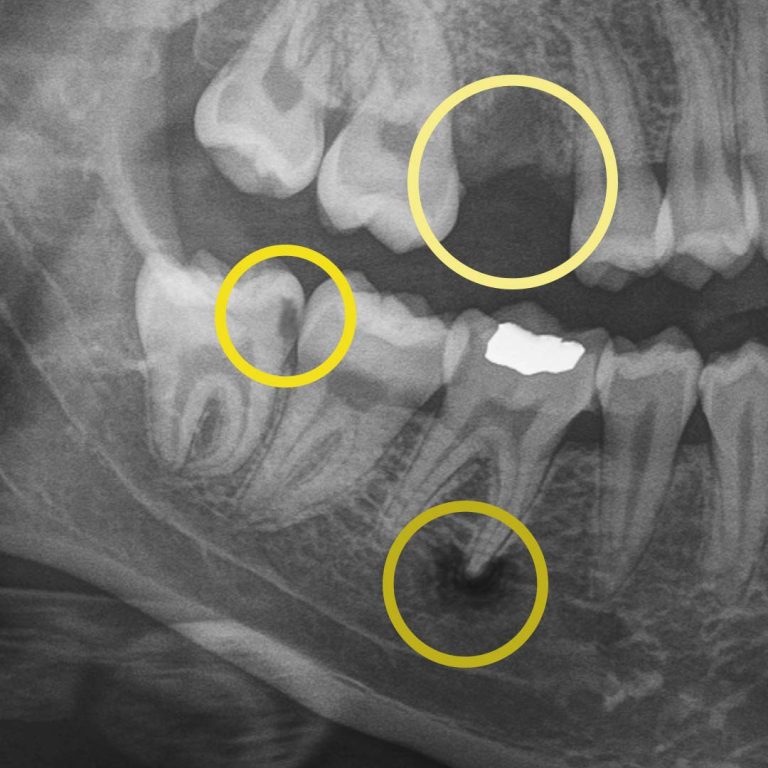

Digital X-rays allow us to see what the human eye simply can’t. They can detect hard and soft tissue changes, and if your dentist uses AI-technology, it can detect changes up to 10x quicker than traditional digital X-rays. More importantly, they help us personalize your care, track your oral health over time, and show you exactly what’s happening, so surprises are limited.

Digital X-rays allow us to look beyond what’s visible. They help us detect:

For example, during a routine digital X-ray, we may notice a small shadow between two teeth. To the naked eye, everything can look healthy, but that faint shadow often tells us the enamel in that area is starting to weaken. This is considered early-stage tooth decay, sometimes called early “caries.”

At your next X-ray visit, we’ll compare images to see whether that spot has stabilized or improved. If the area worsens and the enamel breaks down further, a small dental filling may be necessary to prevent deeper decay damaging the tooth structure. If the decay continues unchecked and reaches the inner portion of the tooth where the nerve lives, treatment becomes more complex, often requiring root canal therapy, which can be time-consuming, uncomfortable, and costly.

While catching early tooth decay is one of the most common reasons we rely on digital X-rays, it’s far from the only one. Dental imaging also helps us monitor bone levels to detect gum disease before it leads to tooth loss, identify disease that can’t be seen during an exam, and track hard and soft tissue changes caused by grinding, acid wear, or dietary habits. A complete set of digital X-rays is necessary every few years to ensure the health of all your teeth. This allows you to keep your natural teeth longer.